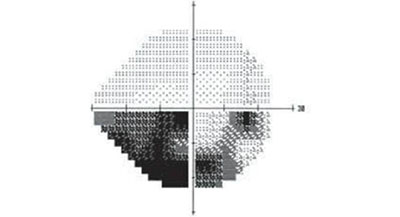

青光眼急性發(fā)作時(shí),由于角膜水腫,同時(shí)瞳孔散大后虹膜不太容易觀察到,患者的眼球呈現(xiàn)的就是這樣的外觀:角膜呈灰綠色,有點(diǎn)放光。所以青光眼三個(gè)字,描繪的是青光眼急性發(fā)作時(shí)眼睛的外觀。